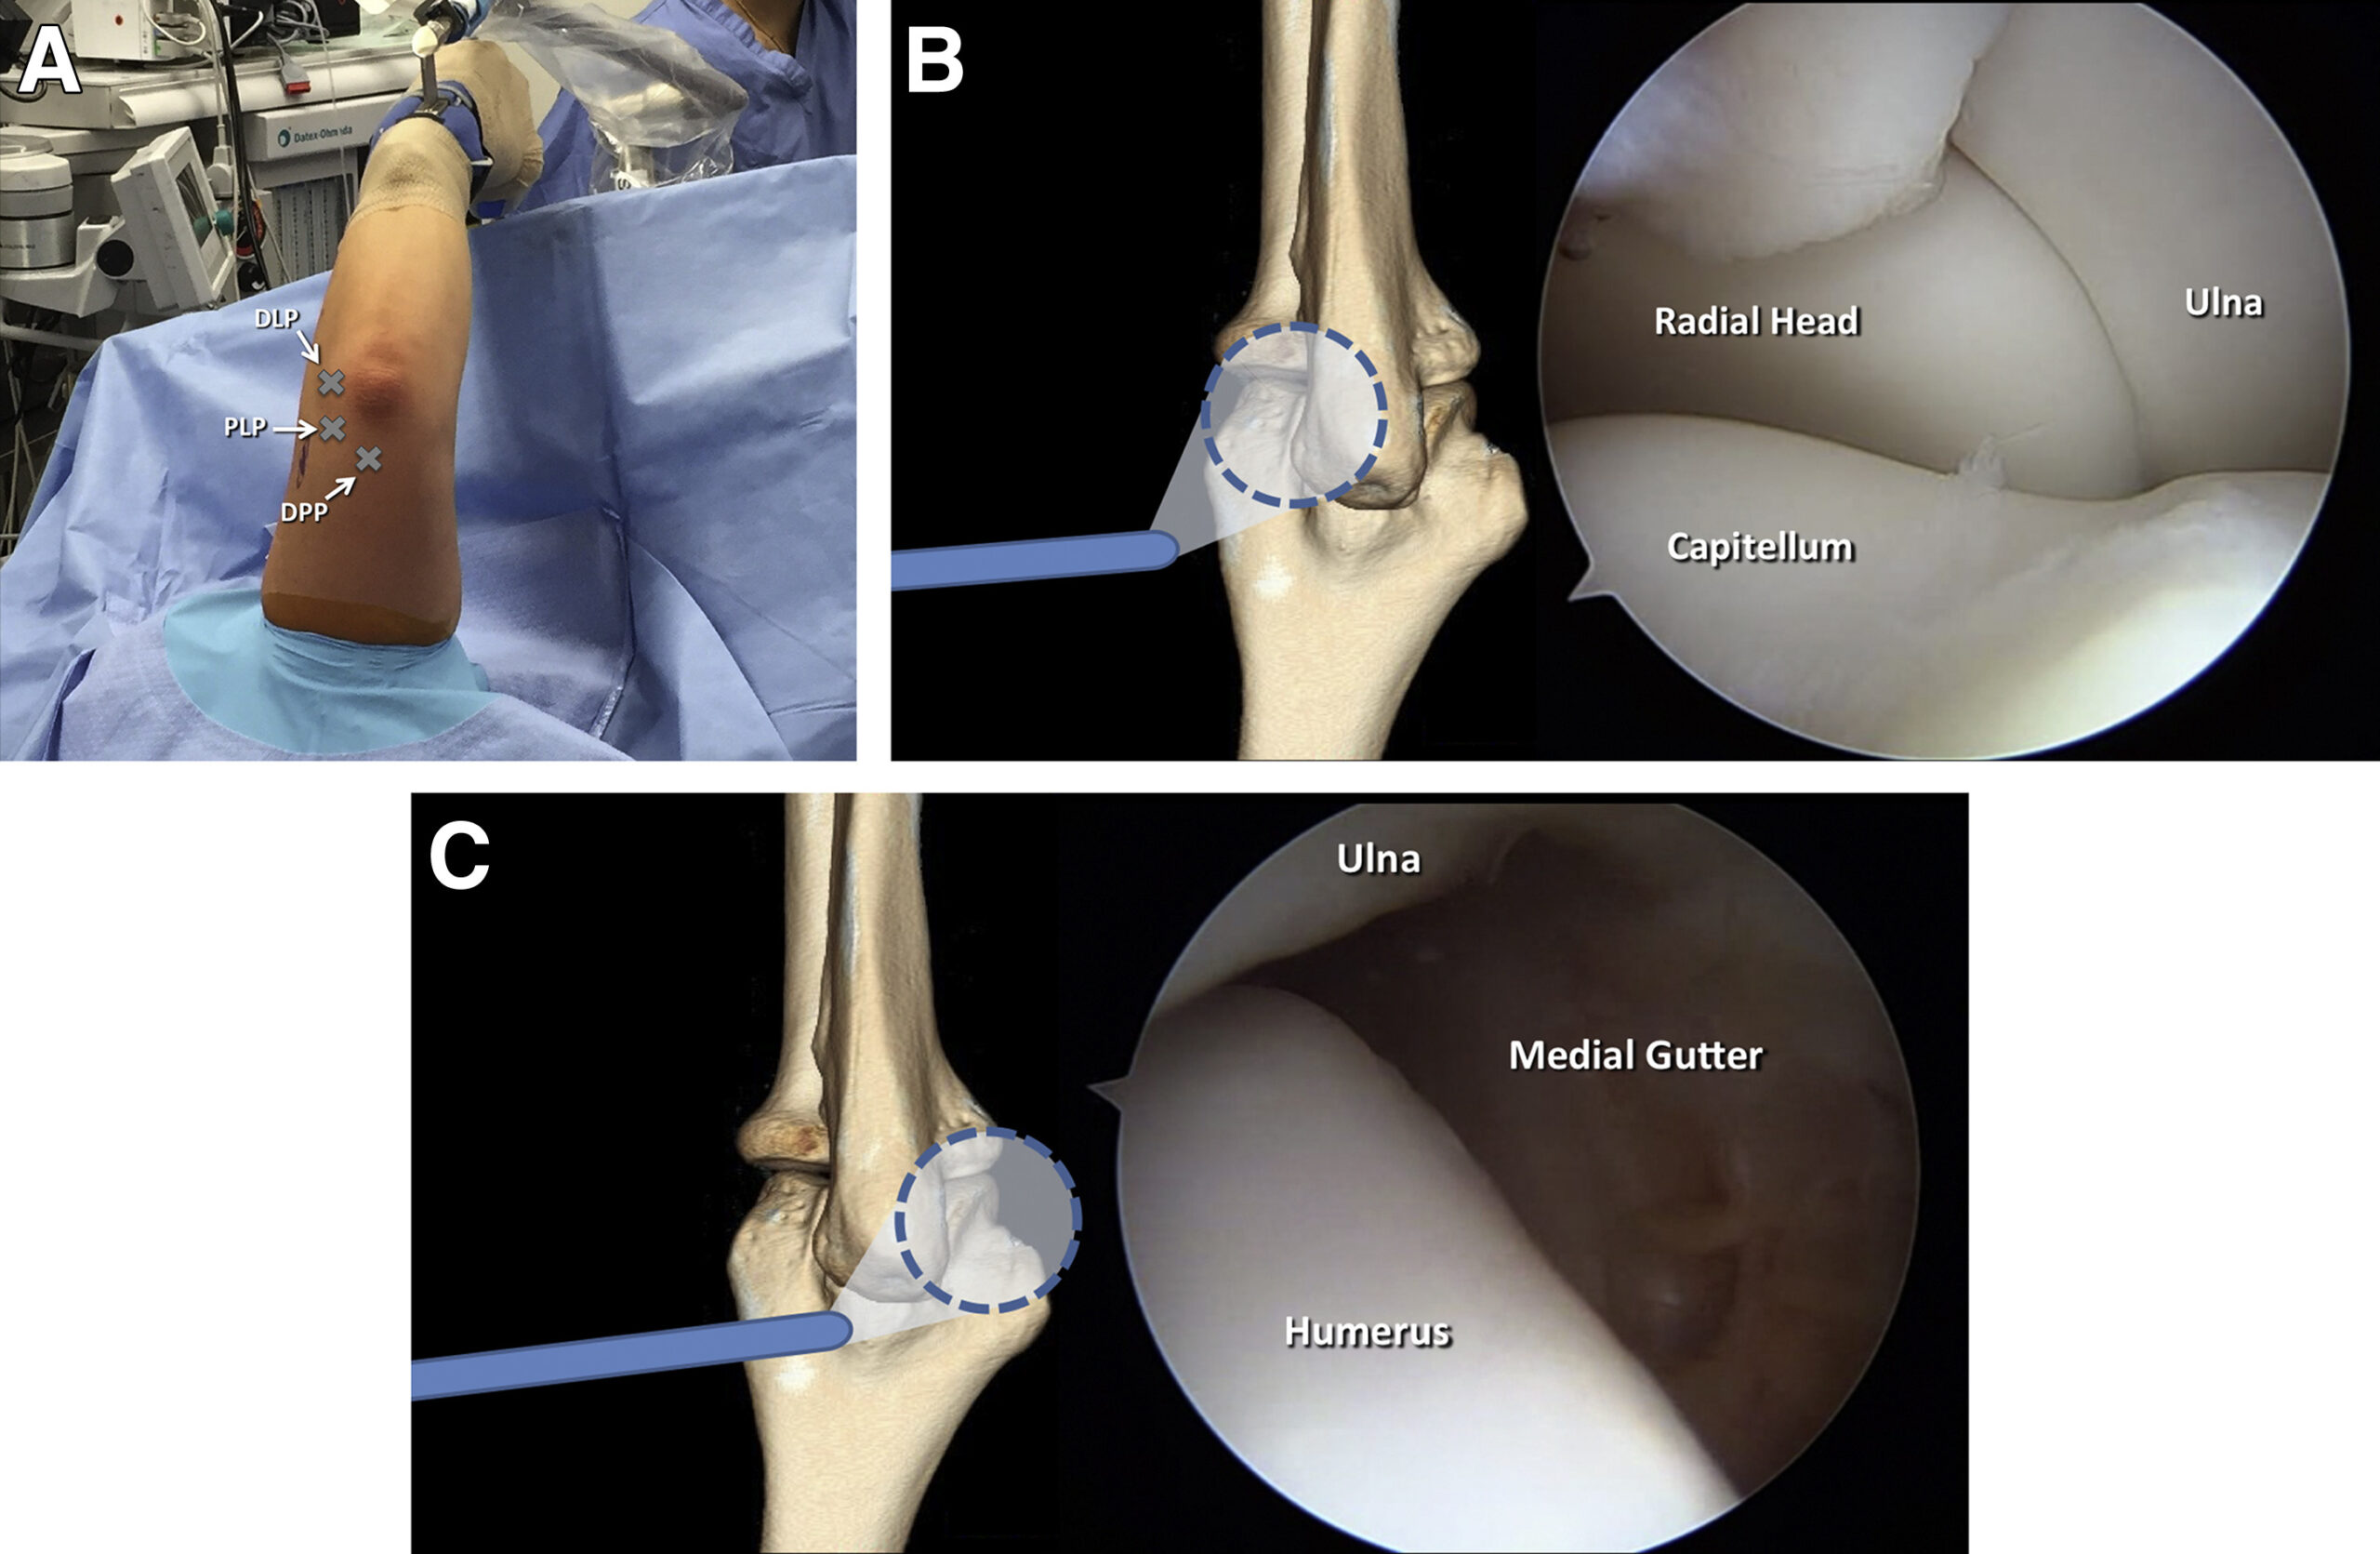

Advanced Elbow Arthroscopy Procedure

Surgeons perform elbow arthroscopy under regional or general anesthesia to ensure patient comfort.

Initially, the surgeon makes two or three small incisions around the elbow joint. After that, a high-definition camera is inserted to examine joint structures.

Meanwhile, specialized surgical tools are introduced to perform treatment procedures.

The surgeon may:

Remove damaged tissue

Repair ligament injuries

Smooth cartilage surfaces

Remove loose fragments

Treat inflammation

Furthermore, surrounding healthy tissues remain preserved during surgery.